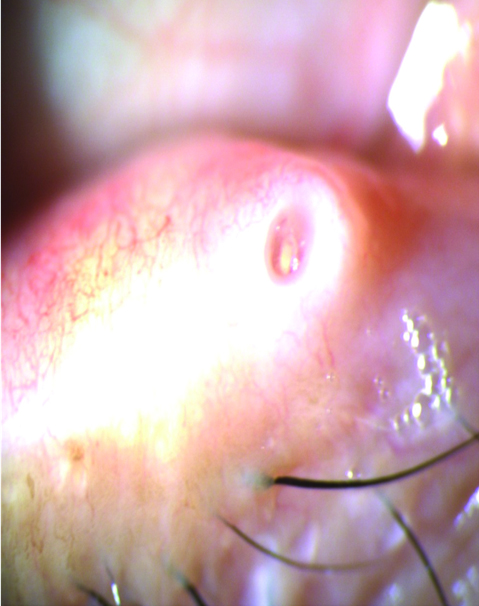

En mi experiencia y opinión personal, sostengo hace largo tiempo que el uso de los denominados tapones lagrimales de silicona pueden agravar los cuadros inmunológicos y/o inflamatorios presentes en el ojo seco, al fomentar los fenómenos inmunocompentes por fricción sobre la superfcie ocular (Figs. 22, 23, 24).

Figura 22: Borde del tapón lagrimal sobre la superficie conjuntival y acúmulos secretorios secundarios.

Figura 23: Borde del tapón deteriorado friccionando la superficie ocular. Secreción, congestión y edema conjuntival.

Figura 24: Contacto del tapón lagrimal en conjuntiva.

Sostuve y sostengo también, que esa fricción crónica puede estimular a los linfocitos conjuntivales y en pacientes susceptibles desencadenar fenómenos de tipo linfoides.

Ambas presunciones han sido recientemente informadas (REF).

Es por ese motivo que prefiero el uso de implantes intracanaliculares profundos de uso extendido o de hidrogel.

He comprobado además en mi práctica que al retirar los tapones lagrimales, los mismos se encuentran con su arquitectura totalmente degradada en un alto porcentaje de los casos (Fig. 25).

Figura 25: Tapón degradado.

Otro factor a tener en cuenta dentro de la problemática del uso de los tapones lagrimales es el cambio anatómico que se produce en la estructura del punto lagrimal. Dilatación, edema, reacciones papilares, inflamación y fibrosis son frecuentes hallazgos (Fig. 26).

Figura 26: Cambios anatómicos en el punto lagrimal al retirar los tapones.